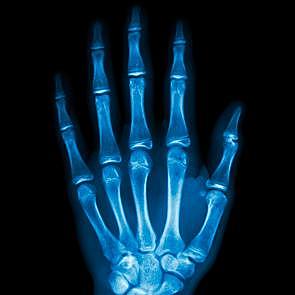

Historia de la Radiología

recubierta por cristales de platino-cianuro de bario. Descubriendo los Rayos X. (3)

En el Hospital Juárez, el Dr. Tobías

Núñez usó este medio diagnóstico por primera vez en una mujer que sufrió un traumatismo en el codo derecho. (2)